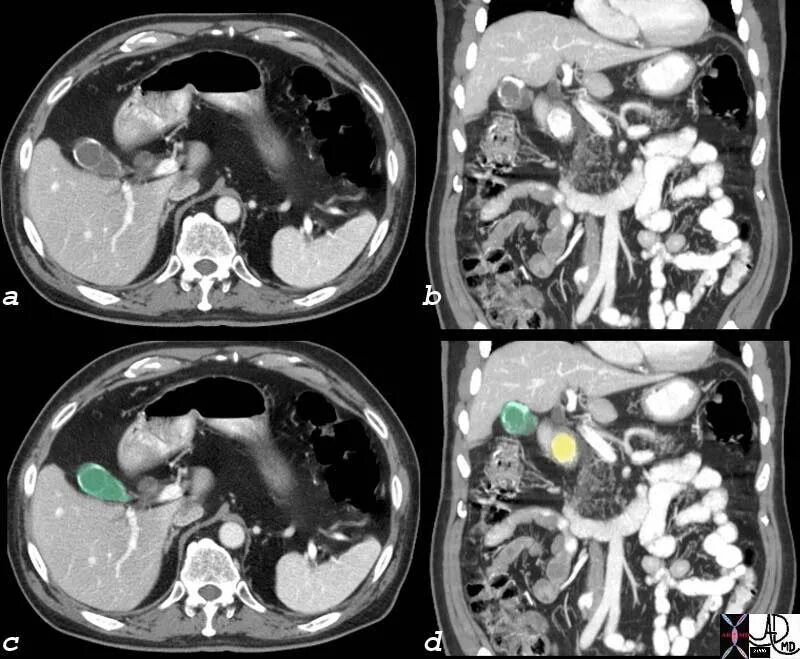

Камни в желчном мрт